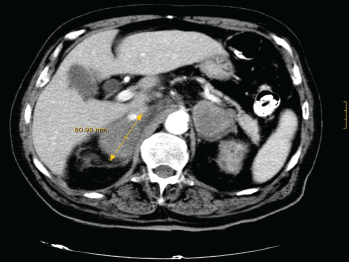

With the suspicion of adrenal insufficiency, he was started on hydrocortisone and fludrocortisone, with progressive clinical improvement and correction of hyponatremia, hyperkalemia, and renal function. During admission he continued to be febrile with spikes of up to 39°C, which resolved with oral naproxen. Baseline serum cortisol levels were 13 mg/dl, with no response to ACTH stimulation. Serum ACTH levels were 217 pg/mL (normal <50 pg/mL), and 24-hour urinary free cortisol was 13 μg (normal, 20–90 μg). An abdominal CT-scan (Figure 1) showed a heterogeneous mass of about 6 cm in diameter in each adrenal gland without other structural abnormalities or lymph node enlargement. F18FDG PET/CT-scan confirmed these findings, and showed high metabolic activity in both tumours, highly suggestive of malignancy.

Figure 1. CT-scan showing a bilateral heterogeneous mass of about 6 cm in diameter in both adrenal glands.